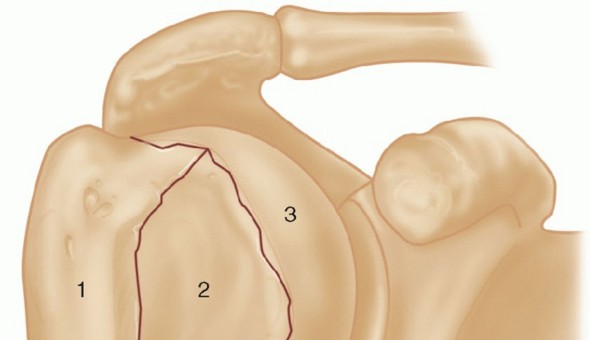

DEFINITION Brett D. Owens Joanna G. Branstetter Thomas P. Goss Intra-articular scapular fractures include fra…